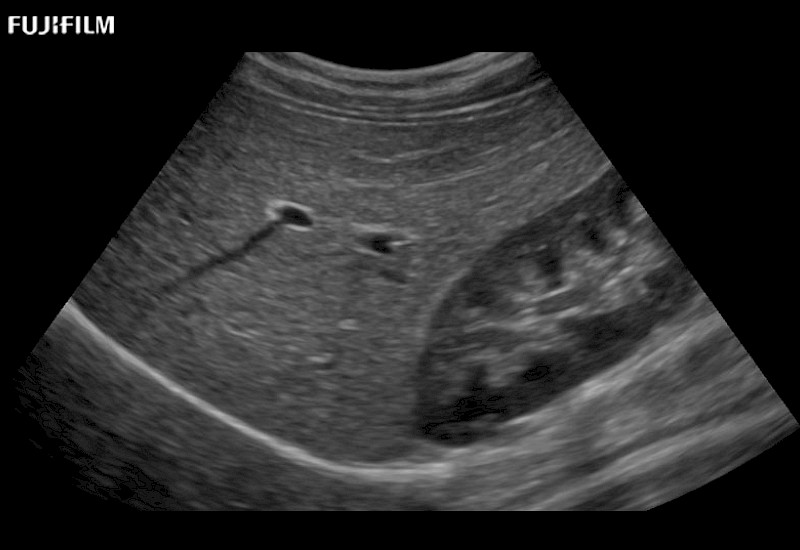

for use during general and laparoscopic procedures: Tumor localization & staging, Ablation, Resection, Biopsy, Transplant, Abdominal exploration, Robotic surgery

Our dedication to Laparoscopic Surgery allows us to offer superior image quality, outstanding system reliability and intuitive use of cutting edge technology.